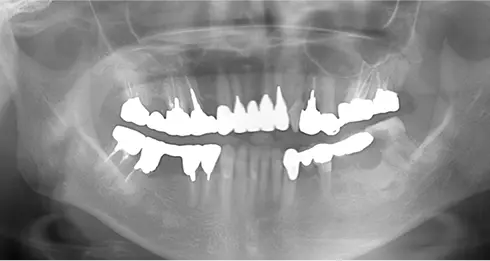

| 年齢/性別 | 40代女性 |

| 主訴 | 右上の詰め物が取れた |

| 治療内容 | 歯周病とむし歯の治療を目的に来院。左下の奥歯は根の状態が悪く、病変も大きかったため保存が困難と判断。 インプラント治療を実施しました。 |

| 治療期間 | 4か月 |

| 費用 | 566,500円税込 |

| リスク・副作用 | 炎症反応によって術後に腫れが生じることがあります。その程度は、手術の範囲や方法によって異なりますが、多くの場合、時間の経過とともに徐々に治まります。 ごく稀に、下顎奥歯の外科手術後に、唇や顎に痺れを感じることがあります。 |